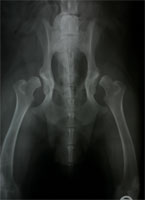

Subluxierende und luxierende Oberschenkelköpfe

Die Autoren der Erstveröffentlichung sind davon ausgegangen, dass bei aus dem Gelenk luxierenden Oberschenkelköpfen die DBO nicht durchgeführt werden dürfe. Sie stelle vielmehr eine Kontraindikation dar. Klinische Erfahrungen mit solchen grenzwertigen Patienten zeigen jedoch, dass Junghunde selbst mit ausgeprägten Subluxationen sehr von der Umstellungsosteotomie profitieren können, weil sich die lockere Gelenkkapsel im postoperativen Verlauf retrahiert und das Gelenk schließlich stabil wird (Abb. 3 a und 3 b). Der Oberschenkelkopf wird zusätzlich mit einem Unterstützungsband (Meij-Technik, Abb. 4) in das rotierte Acetabulum hineingezogen. Zusätzlich hat sich der Einsatz der 40° Platte bewährt. Der im Hüftgelenk nun festen Halt findende Femurkopf übt zudem einen positiven formativen Reiz auf die noch wachsende Pfanne aus, den man als Spreizhosen-Effekt bezeichnet. Als Ergebnis sind stabile Gelenkverhältnisse zu erwarten.

HD luxierte Oberschenkelköpfe

Abbildung 3 a: Vollständig luxierende dysplastische Hüftgelenke

DBO bei luxierten Femurköpfen

Abbildung 3 b: Der selbe grenzwertige Patient nach DBO und Unterstützungsband nach Meij.